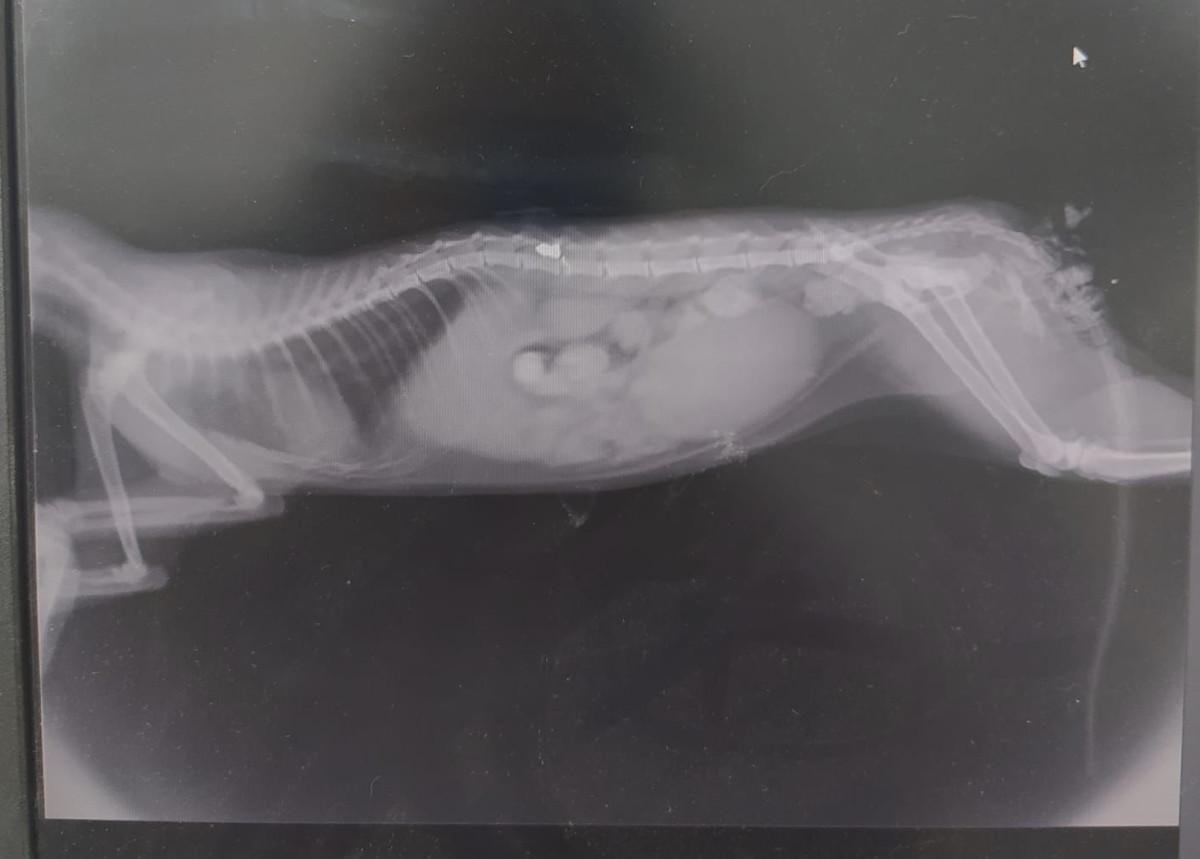

OMURİLİĞİNDE HAVALI TÜFEK MERMİSİ BULUNDU

Kediyi veterinere götüren Ermiş, burada çekilen röntgende kedinin kazada yaralanmadığını, omuriliğinde havalı tüfek mermisi bulunduğunu ve durumunun kritik olduğunu öğrendi.

Operasyonla birlikte, omurilikte bulunan ve yürüme duyularına zarar veren saçma çıkarılarak kedinin fizik tedavisine başlandı.